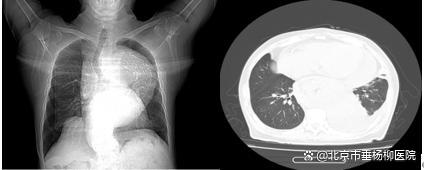

图表2 一位尚未透析的终末期肾脏病患者

也就是我们常说的“围透析期”,通常发生在刚开始透析,或者透析不充分的患者身上透析不充分,我们图中第二例患者就是一位未及时开始透析的终末期透析患者。如果透析次数不够、时间不足,毒素清除得不够理想,依然会持续刺激心包。